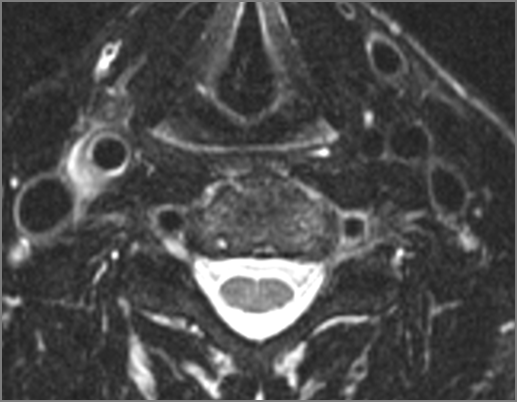

There is edema/abscess within in the prevertebral or paravertebral spaces. [Yes/No]

There is edema/abscess within in the epidural space. [Yes/No]

There is erosive process involving the disc spaces or other components of the spine. [Yes/No]